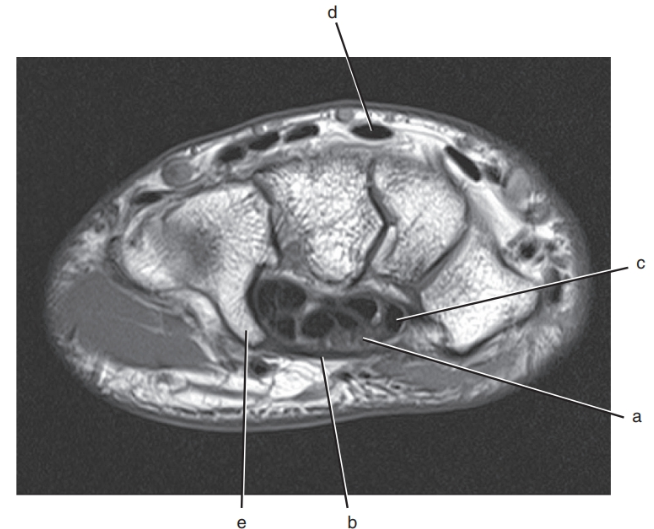

What is letter a?

Median nerve

What is letter e ?

Hook of the hamate